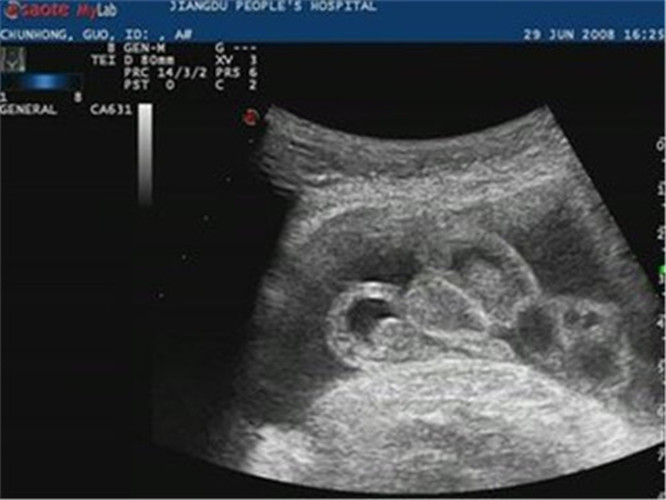

胎兒尿道下裂B超